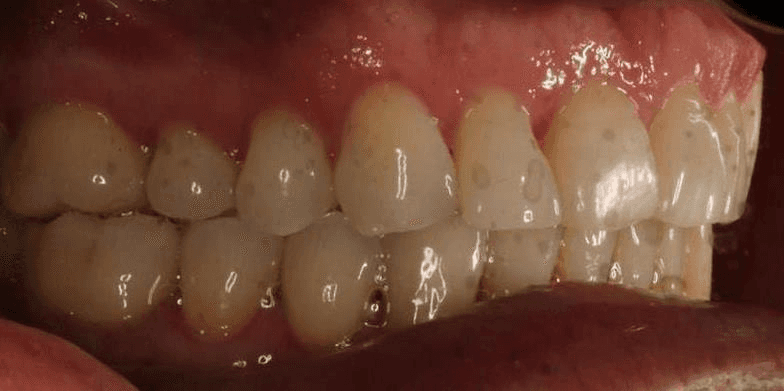

INTRAORAL